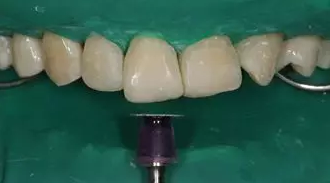

病例分享|復合樹脂微創(chuàng)美學修復關閉上前牙間隙

牙體微預備